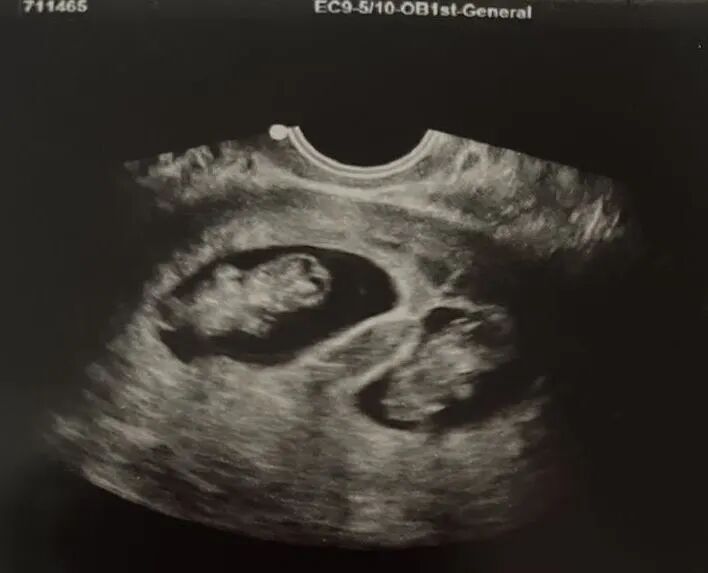

移植多个胚胎会有更高的受孕几率,但也会稍带更高的孕期风险。我们最近已经欢迎了许多双胞胎宝宝,已经开始充满期待,希望不久后能收到爱妈的好消息!